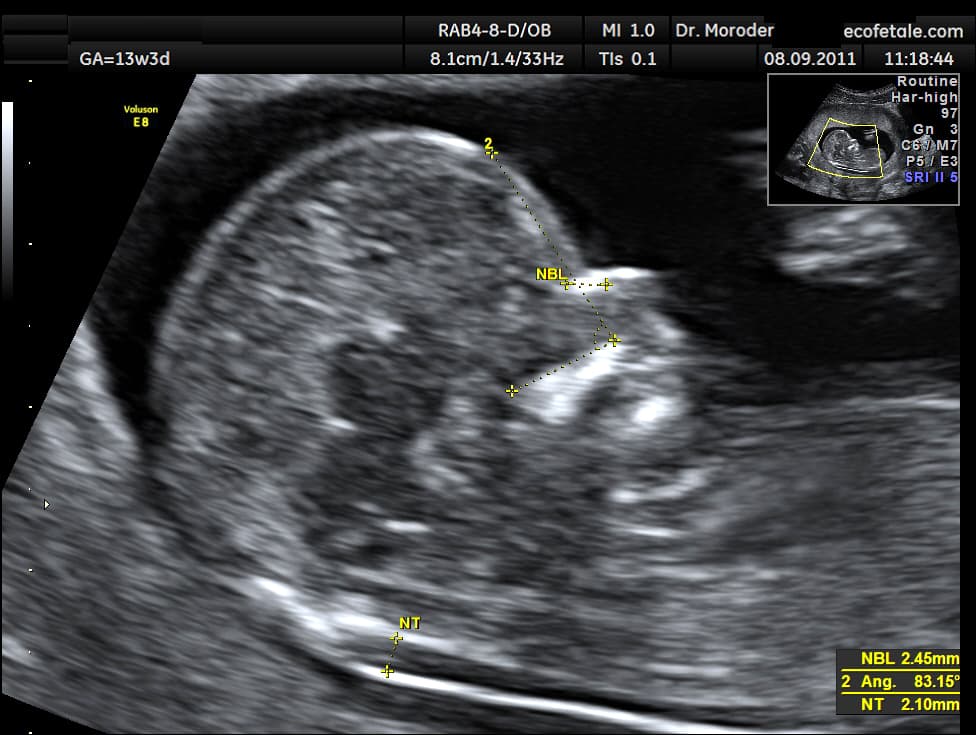

A nuchal scan or nuchal translucency (NT) scan/procedure is a sonographic prenatal screening scan (ultrasound) to detect chromosomal abnormalities in a fetus, though altered extracellular matrix composition and limited lymphatic drainage can also be detected. Since chromosomal abnormalities can result in impaired cardiovascular development, a nuchal translucency scan is used as a screening, rather than diagnostic, tool for conditions such as Down syndrome, Patau syndrome, Edwards Syndrome, and non-genetic body-stalk anomaly. There are two distinct measurements: the size of the nuchal translucency and the thickness of the nuchal fold. Nuchal translucency size is typically assessed at the end of the first trimester, between 11 weeks 3 days and 13 weeks 6 days of pregnancy. Nuchal fold thickness is measured towards the end of the second trimester. As nuchal translucency size increases, the chances of a chromosomal abnormality and mortality increase; 65% of the largest translucencies (>6.5mm) are due to chromosomal abnormality, while fatality is 19% at this size. A nuchal scan may also help confirm both the accuracy of the pregnancy dates and the fetal viability. All women, regardless their age, have a small chance of delivering a baby with a physical or cognitive disability. The nuchal scan helps physicians estimate the chance of the fetus having Down syndrome or other abnormalities more accurately than by maternal age alone. Down syndrome Overall, the most common chromosomal disorder is Down syndrome (trisomy 21). The likelihood rises with maternal age from 1 in 1400 pregnancies below age 25, to 1 in 350 at age 35, to 1 in 200 at age 40. Until recently, the only reliable ways to determine if the fetus has a chromosomal abnormality was to have an invasive test such as amniocentesis or chorionic villus sampling, but such tests carry a risk of causing a miscarriage estimated variously as ranging between 1% or 0.06%. Based on maternal age, some countries offer invasive testing to women over 35; others to the oldest 5% of pregnant women.